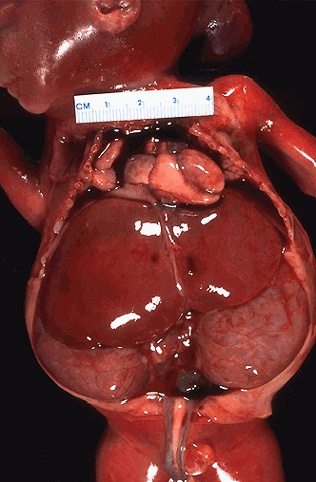

Image 3.4

The abdominal cavity is shown here. What are the large bilateral structures?